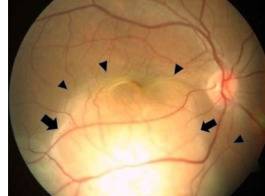

![온몸에 전이된 페암의 첫 증상으로 실명한 30대 여자 환자의 오른쪽 안구. 검은 화살표 부위에서 눈으로 전이된 암이 발견됐다. [Radiology Case Reports 캡쳐]](https://img3.daumcdn.net/thumb/R658x0.q70/?fname=https://t1.daumcdn.net/news/202507/18/KorMedi/20250718180544324orxp.jpg)

다시 정밀 검사를 하던 의료진은 오른쪽 눈 뒤쪽에서 희끄무레한 황색 덩어리를 발견했다. 또 빛에 민감한 부분인 망막 아래에 액체가 고여 있었다. 왼쪽 눈에도 비슷하고 작은 병변이 있었다. 다만 망막은 손상되지 않은 상태였다.

의료진은 마지막으로 흉부 X-레이와 전신 스캔을 통해 여성의 오른쪽 폐 아랫부분에서 자라는 암 덩어리를 발견했다. 이 종양은 맥락막(choroid)이라 불리는 안구벽을 포함해 다른 여러 장기로 퍼져 있었다. 암이 눈으로 전이되면 대부분 맥락막에 종양이 붙는다. 폐암에선 이런 경우가 매우 드물다.

맥락막은 망막과 공막 사이에 위치한 안구벽 중 하나로, 망막을 통해 외부에서 들어온 빛이 분산되지 않도록 한다. 아울러 맥락막에 분포한 혈관은 망막에 영양분을 공급한다.